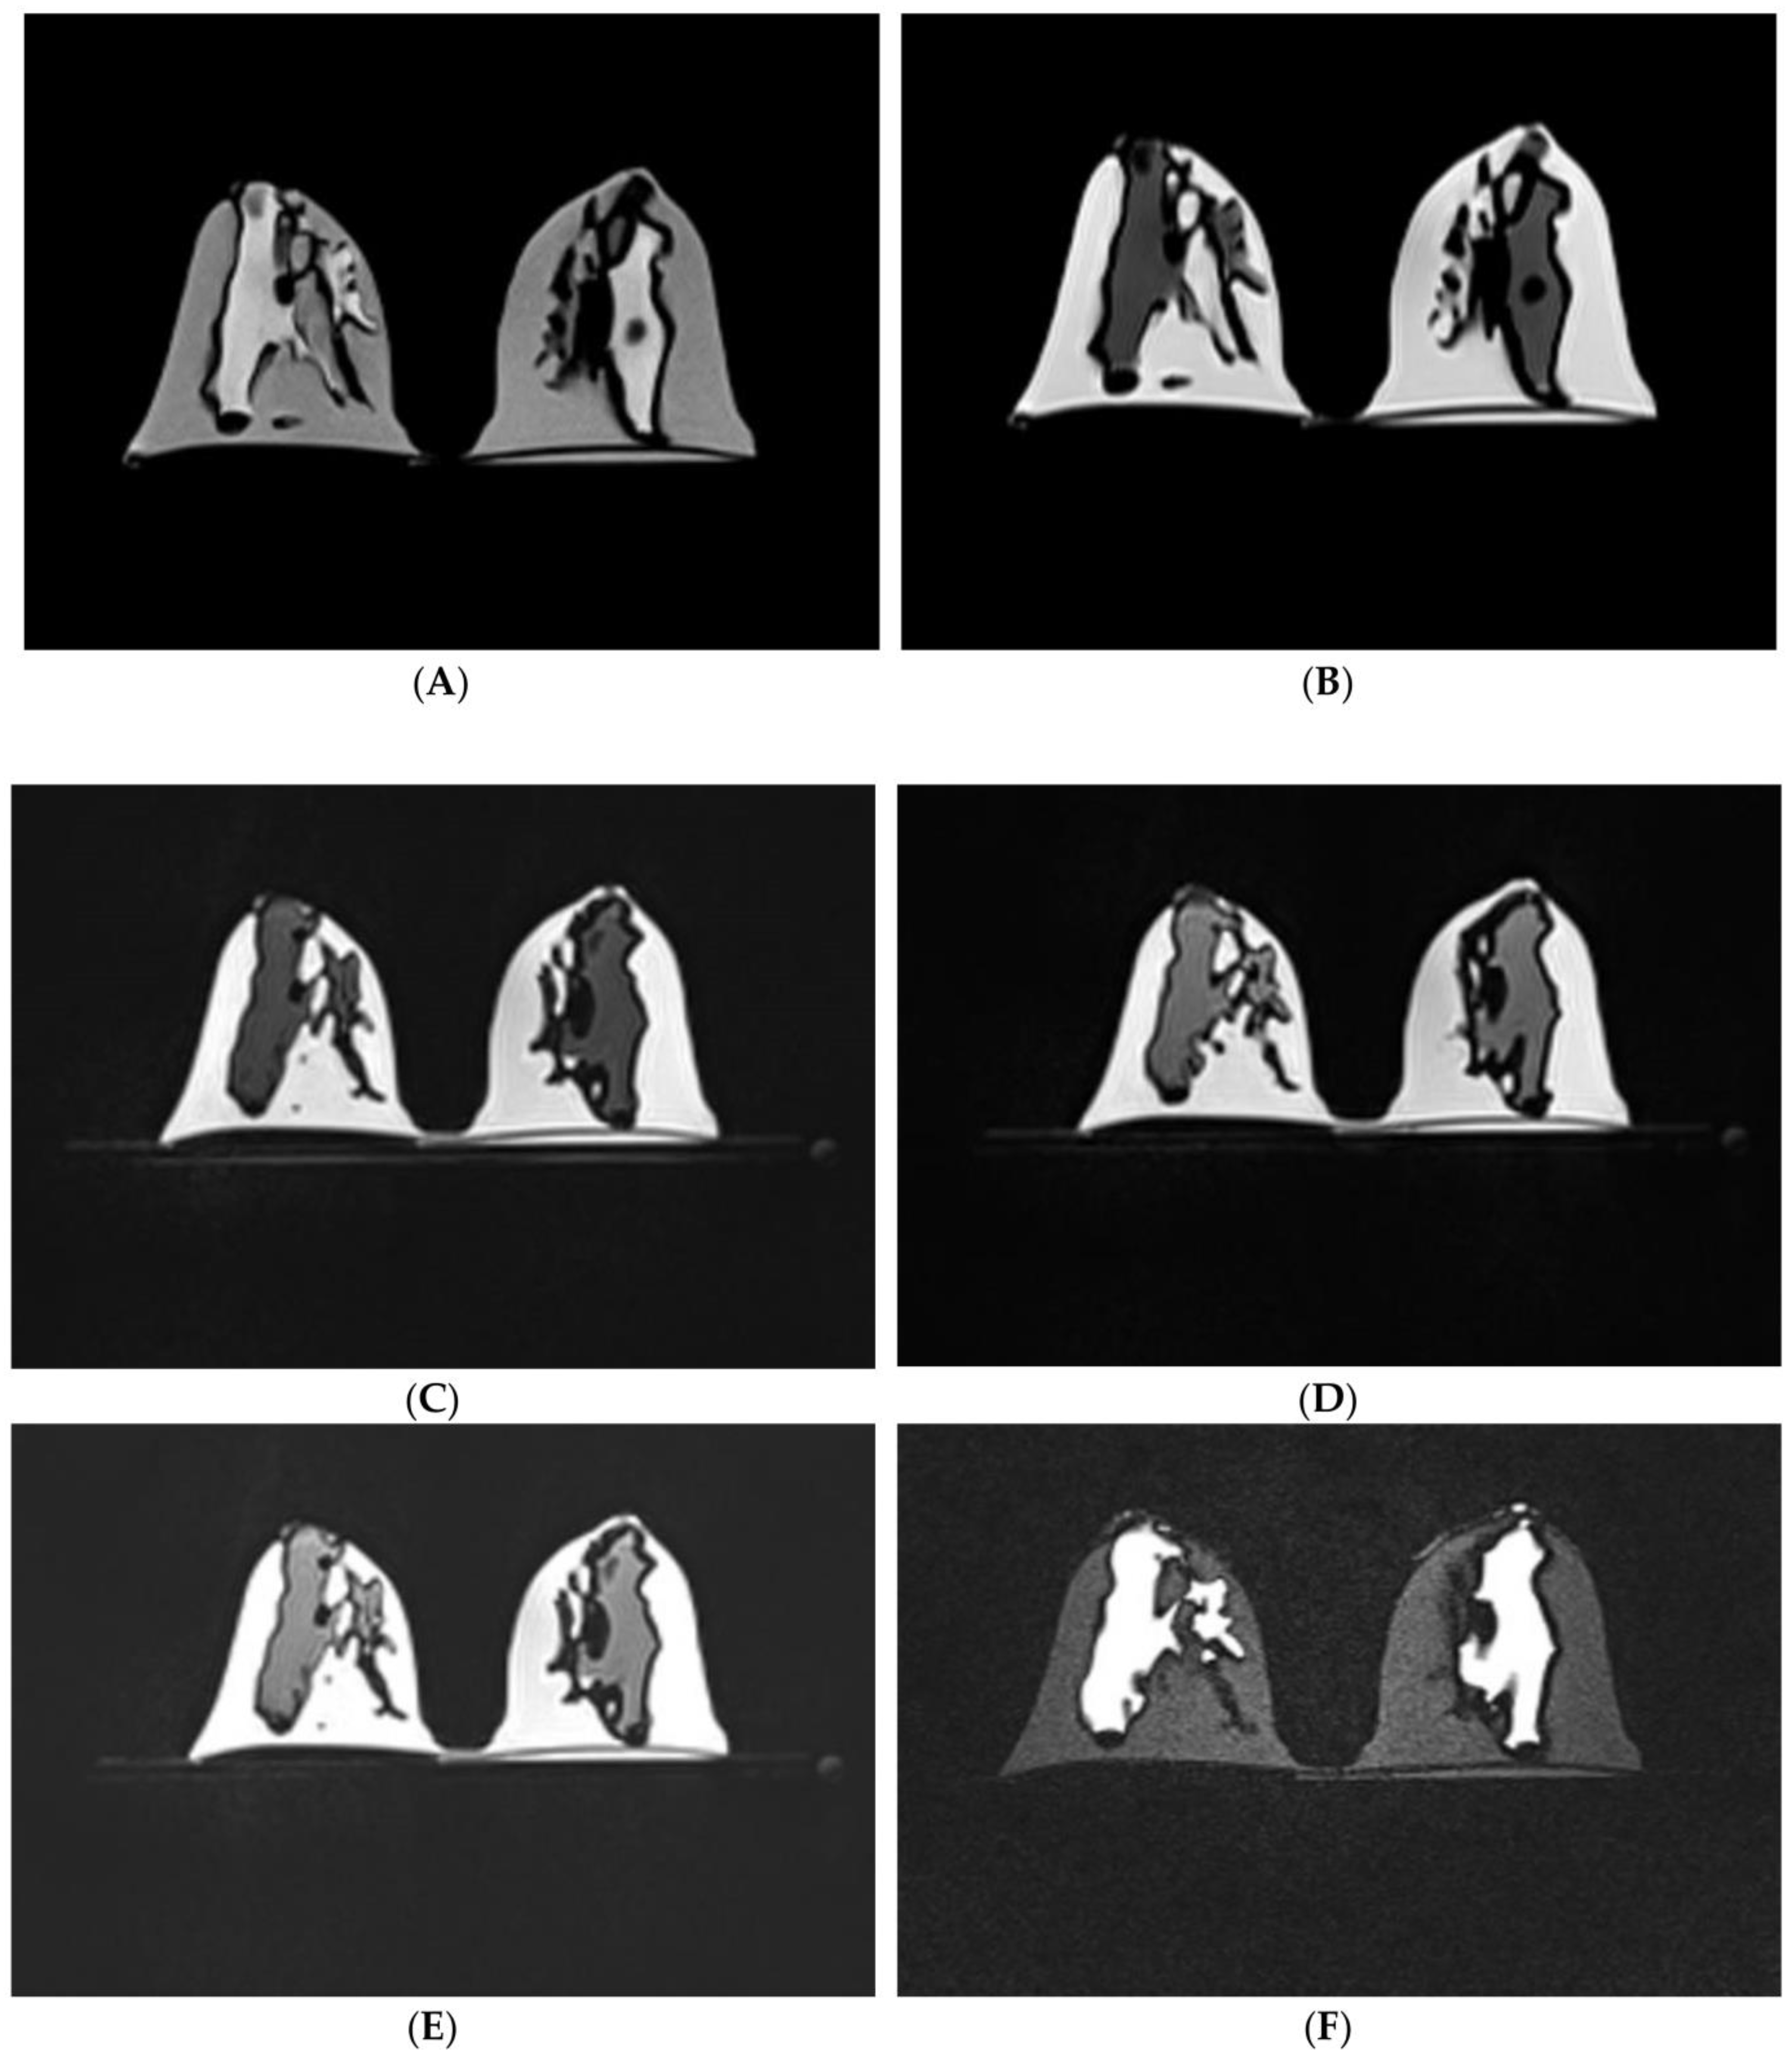

5.6. 3D-Printed Chest Models

| Chest (lungs, thoracic vertebral column and ribs) | 1 with three compoents: lung shell, thoracic ribs/vertebrae and trachea | CT | Creation of anatomical environment for cardiovascular imaging studies | Printer: Thoracic ribs and lung shell were printed using Raise3D N2 Plus; Trachea was printed using Ultimaker 2+ Extended Materials: Thoracic ribs/vertebrae and lung shell were printed with PLA Trachea was printed with TPU 95A. Cost: USD 75 for thoracic ribs and lung shell; USD 10 for trachea | Thoracic ribs and lung shell were printed at a resolution of 12.5 μm for the x and y-axis planes; 10 μm for z-axis plane Trachea was printed at a resolution of 12.5 μm for the x, y and z-axis planes Time: ~450 h for thoracic ribs and lung shell; ~17 h for trachea |